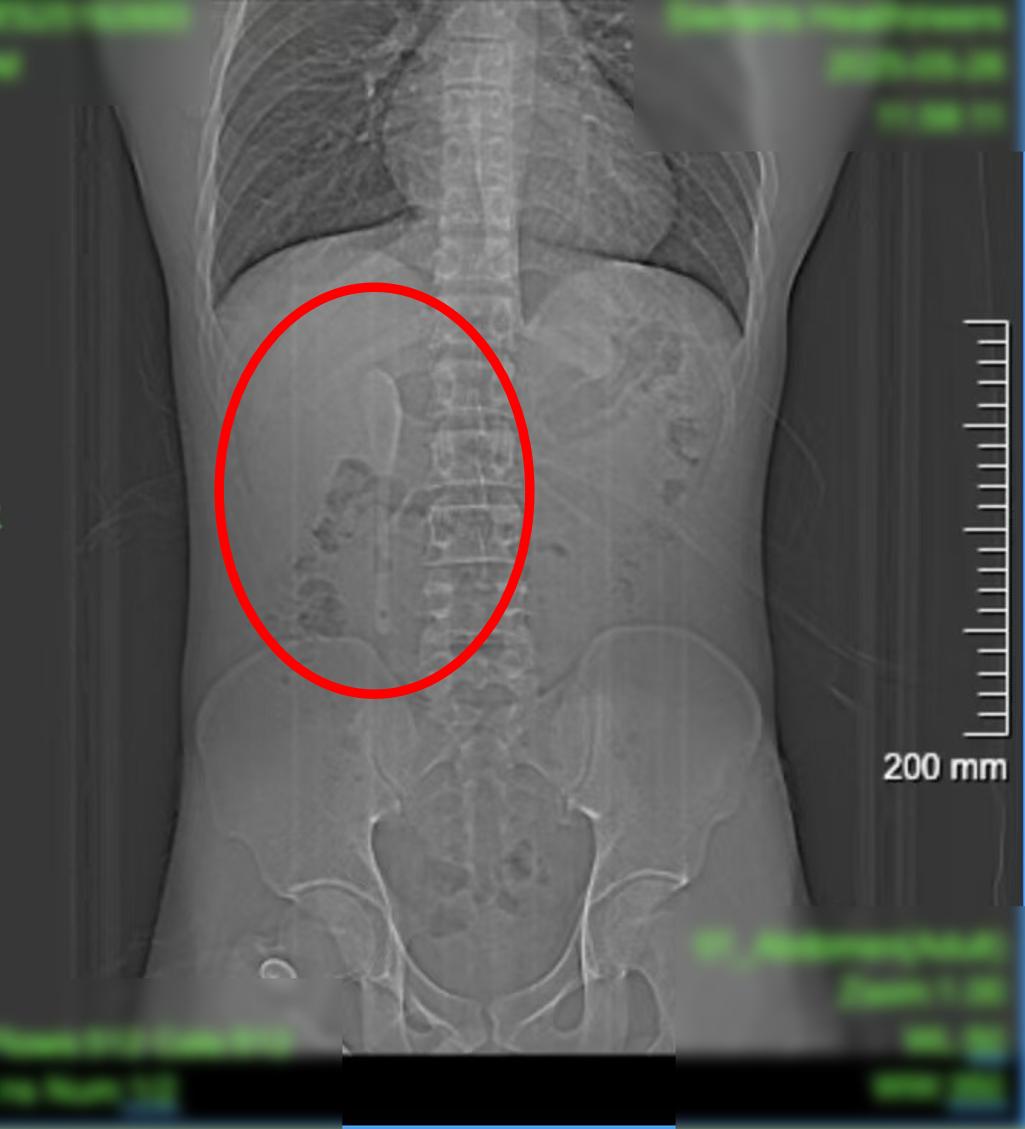

CT显示这支近15厘米长勺状物体,严丝合缝地横亘于十二指肠球部与降部交界的生理狭窄处,稍有不慎即可能刺穿肠壁,引发腹膜炎或大出血。更离奇的是,身为严格自律的健身人士,小言对此毫无记忆。

这支被遗忘的勺子,历经6个月胃肠蠕动,最终精准卡进十二指肠球部与降部交界处。此处腔隙狭窄且肠壁极为菲薄,异物极易嵌顿,稍有不慎容易造成穿孔。中山医院内镜中心主任周平红教授解释:“勺子陶瓷质地光滑细长,十二指肠球降交界又是人体上消化道的生理狭窄处,内镜下取出难度极大。若失败,只能开腹手术。”